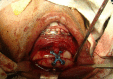

Facial asymmetry is one of the commonest facial anomalies, with reported incidence as high as 34%. Hemifacial microsomia (HFM) has an incidence of 1 in every 4000-5600 children and is one of the commonest causes of facial asymmetry. The standard treatment of HFM is orthognathic surgery by bilateral saggital split osteotomy (BSSO) or distraction osteogenesis (DO) of the mandible, both of which involve prolonged periods of occlusal adjustments by an orthodontist. Here, we present distraction of the mandible by means of a novel modified step osteotomy to correct the facial asymmetry in a case of hemifacial microsomia without disturbing the occlusion. This novel technique can prove to be a new tool in the maxillofacial surgeons armamentarium to treat facial asymmetry.